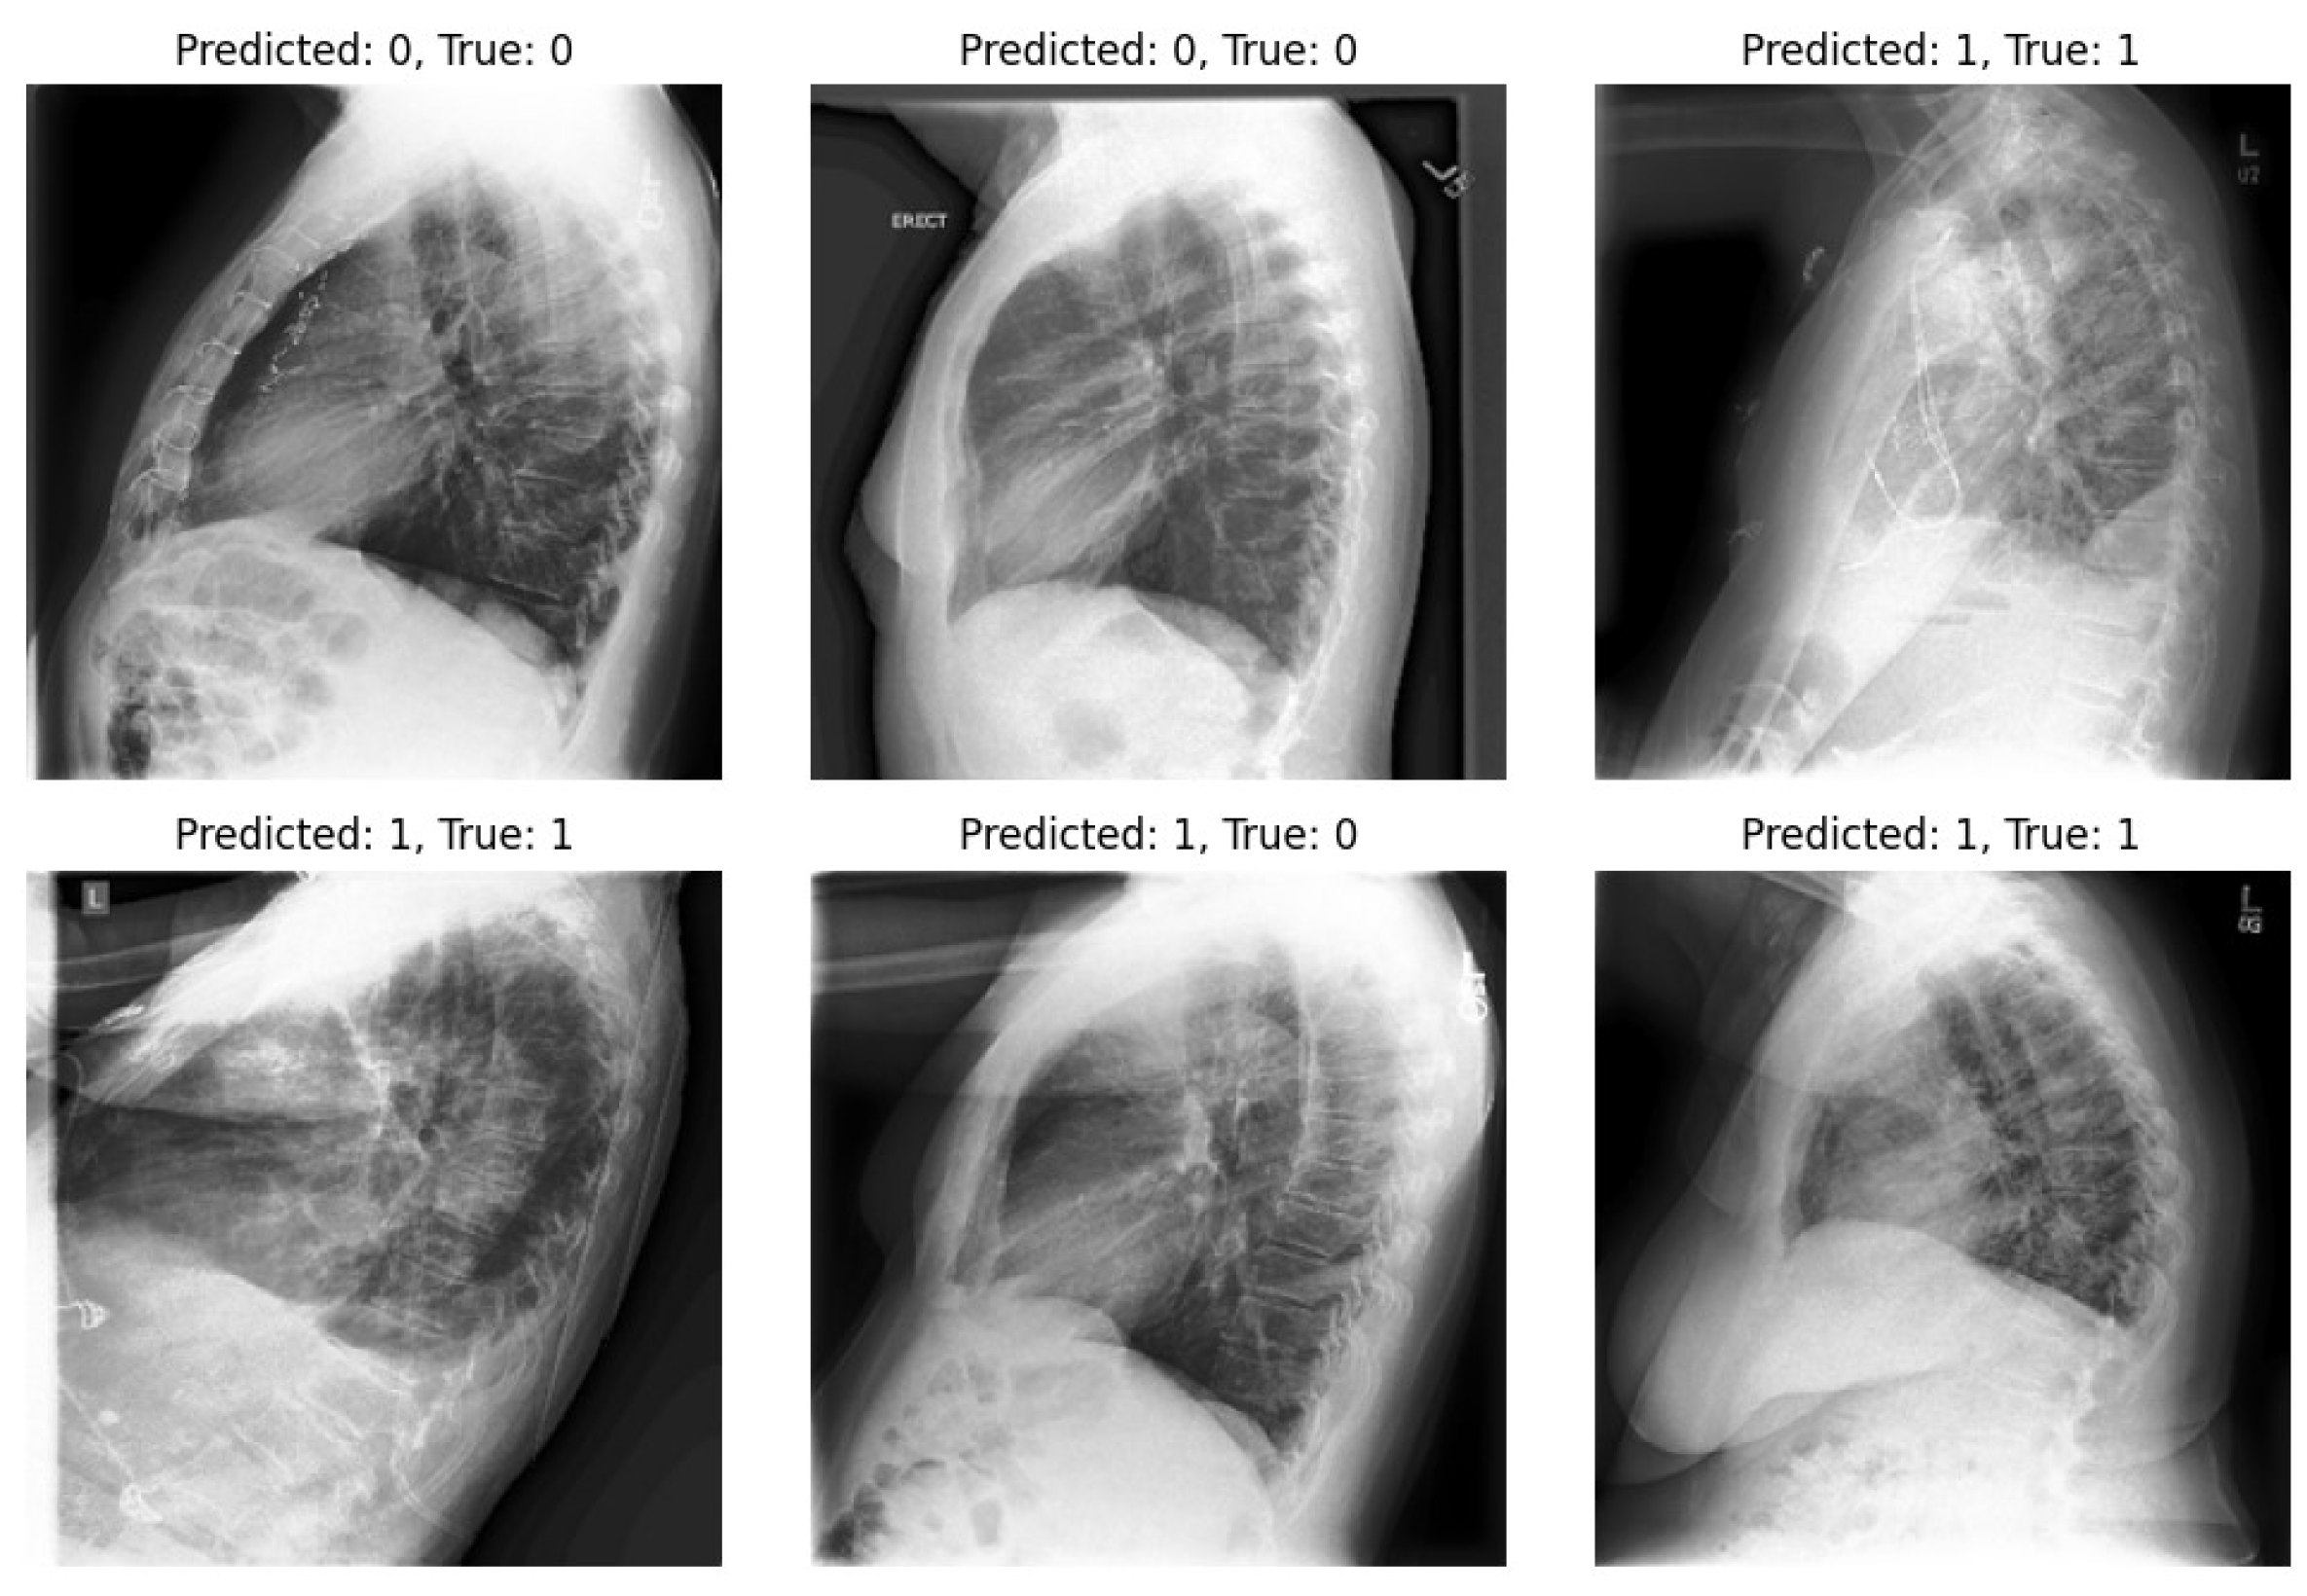

Our study underscores the pivotal role of multi-view X-rays in augmenting the reliability of disease diagnosis, particularly in the case of pneumonia. Our experiments validate the significance of incorporating lateral-view X-rays alongside frontal ones for more comprehensive assessments, thereby enhancing the overall reliability of the diagnostic process and facilitating more confident clinical decisions. By integrating latent representations derived from both the VAE and β -VAE models, our approach significantly enhances diagnostic outcomes in pneumonia classification tasks. On the other hand, we highlight one of the limitations of our experiments: the imbalance within our dataset. Notably, in the experiments, the number of positive samples was twice that of negative samples. This imbalance stemmed from the scarcity of images devoid of the disease and offering diverse viewpoints within the dataset. The classifier’s performance is illustrated in Figure 9 and Figure 10, revealing instances where the model erroneously classified negative images as positive when evaluating the test set. Despite these challenges, our methodology shows promising performance and yields satisfactory results compared to previous studies.

Figure 10. Utilizing a classifier to predict lateral images from the test set.

Diagnostics 14 01566 g010